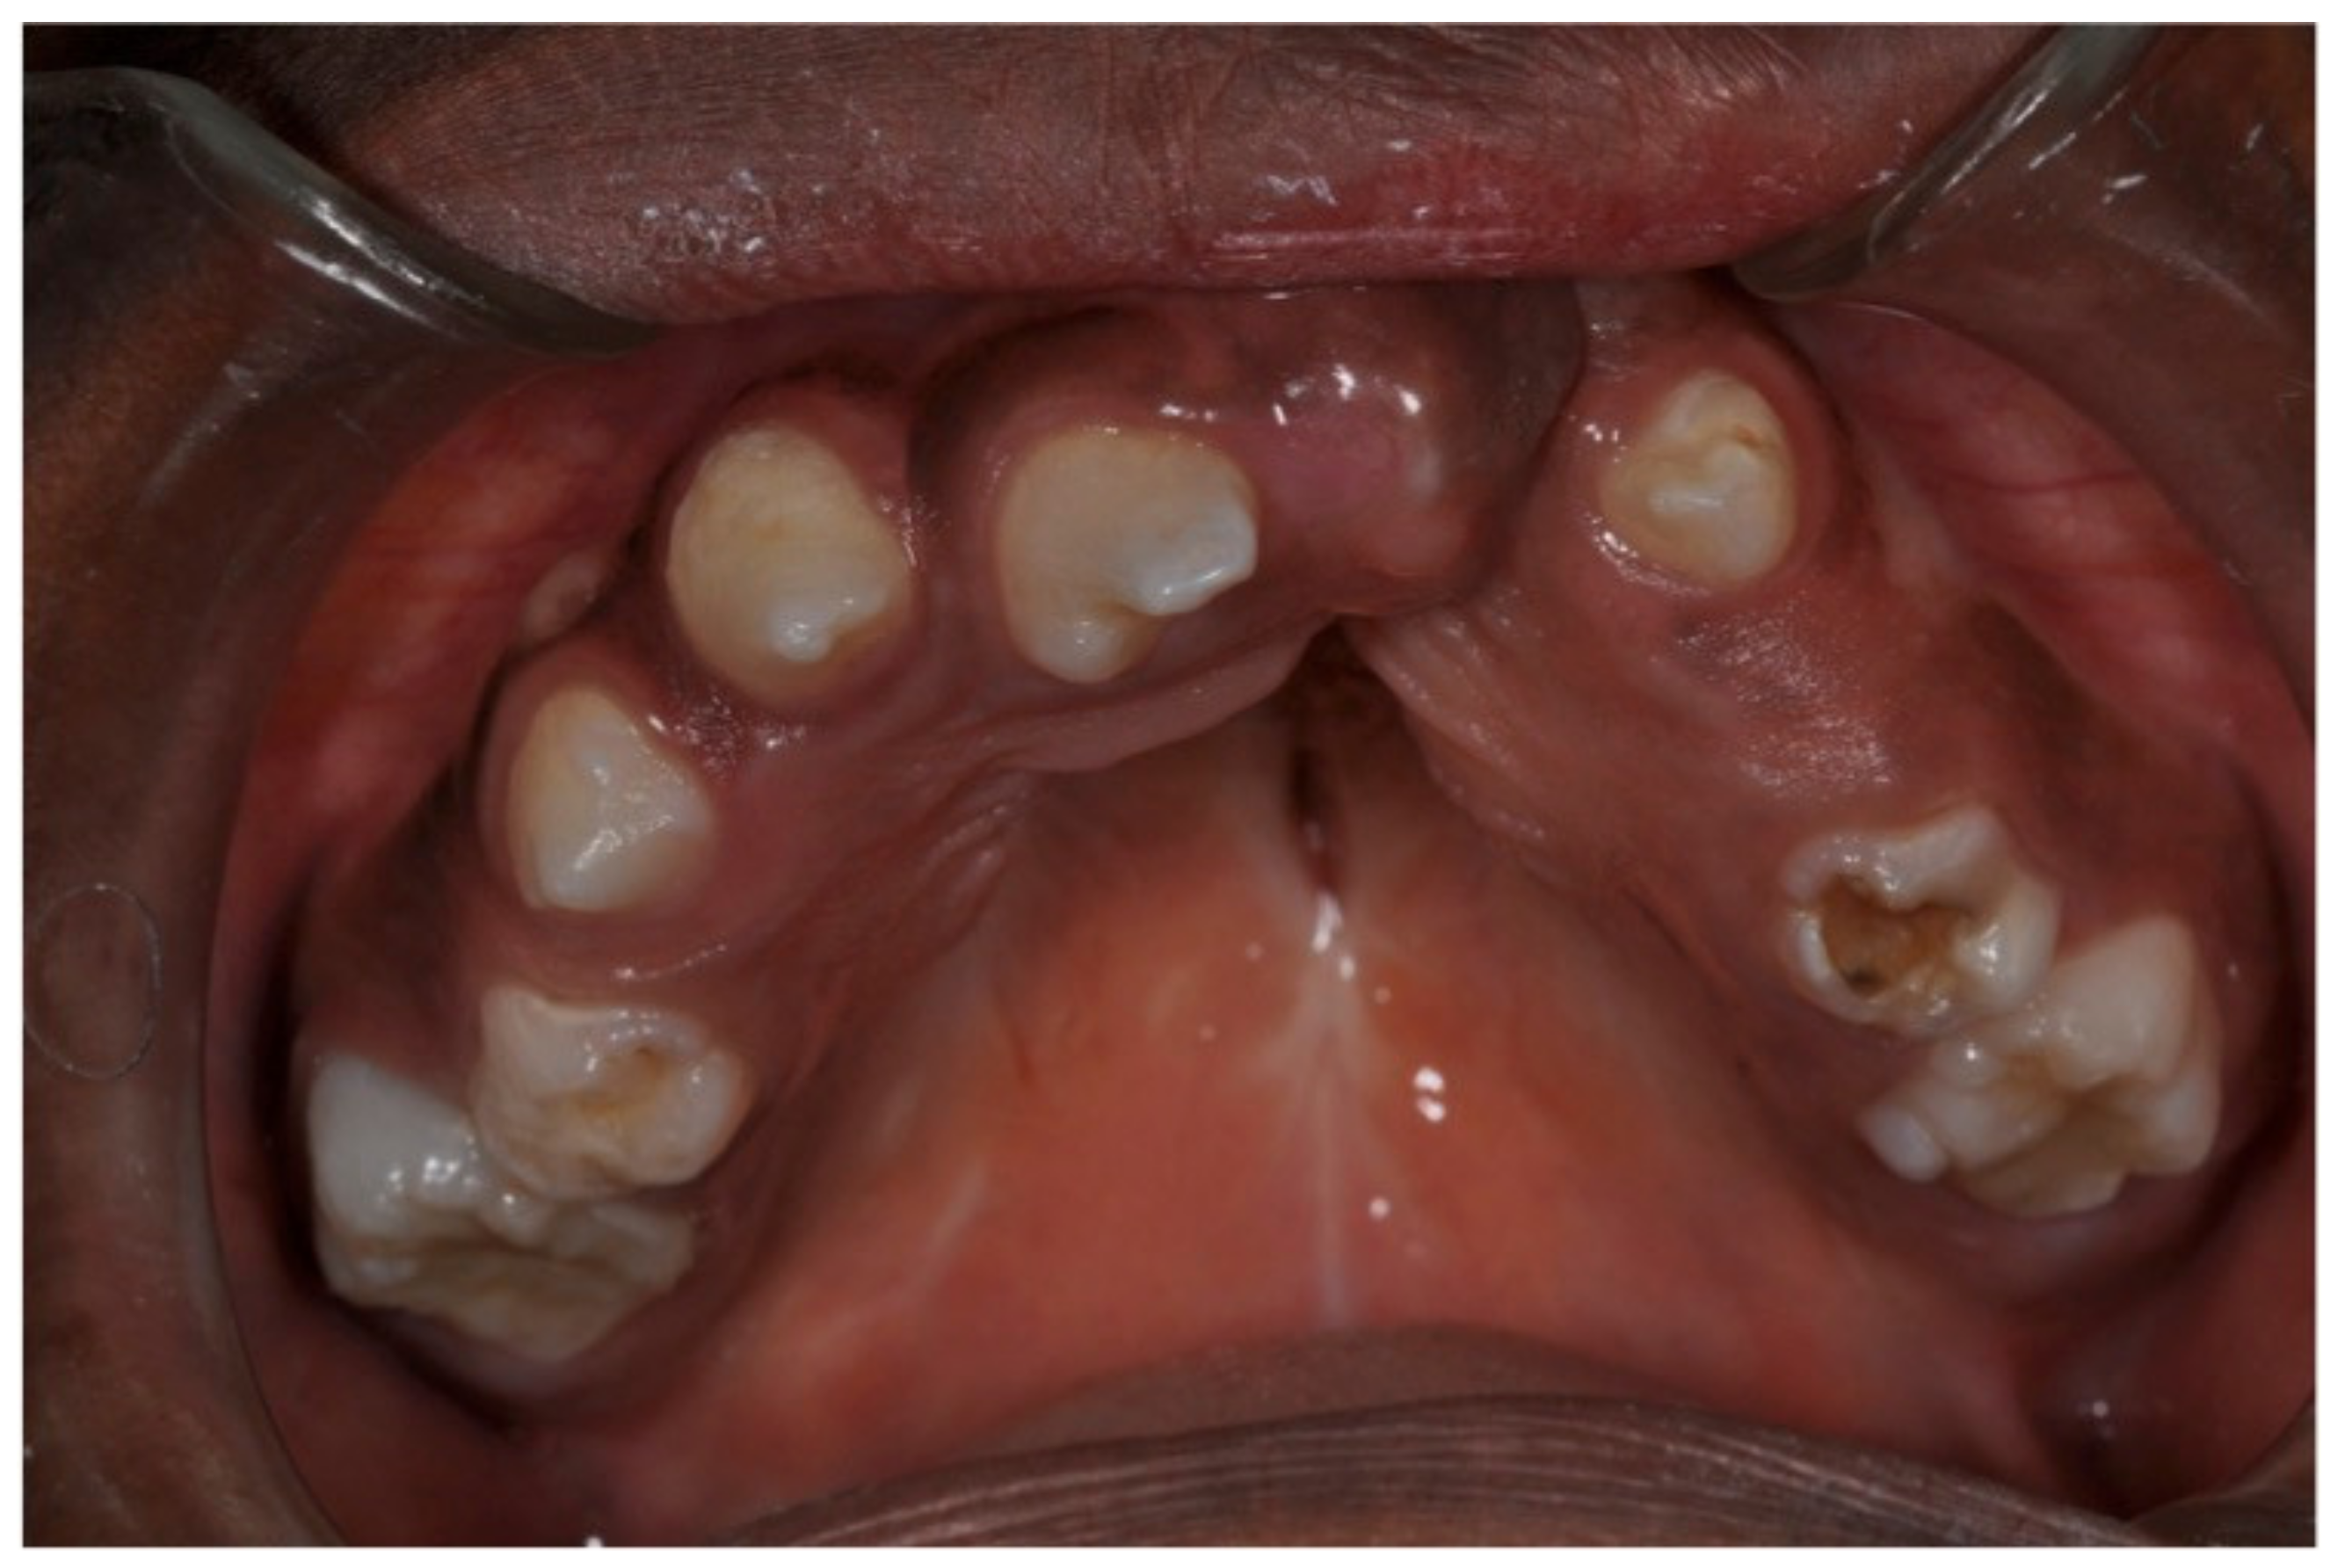

3.2. Pediatric Dentistry Specialist Management of Dental Anomalies in Children with CLP